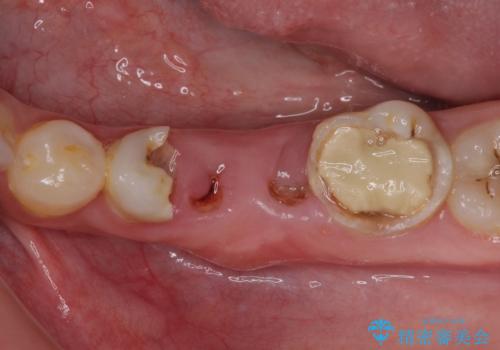

むし歯だらけの奥歯 セラミッククラウンによるむし歯治療

- 奥歯のむし歯を気にして来院された患者様です。

痛みのある歯が多く、根管治療が必要と診断されました。

左下の歯は、クラウンを装着するために必要な高さが足りないため、歯冠長を延長するための外科処置を行うこととしました。

根管治療や歯周外科処置後にフルジルコニアクラウンにて補綴治療することとしました。

自身の口腔内への意識が高くなく、汚れが非常に多い方でした。